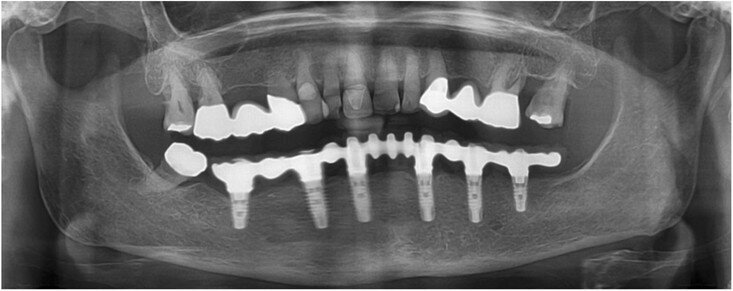

Fig. 15: Panoramic radiograph at delivery of the final CAD/CAM FDP.

All six implants osseointegrated successfully without complications. After six months of the patient wearing the provisional FDP, a conventional impression was taken (screw-retained impression copings, open-tray technique, polyether material) to fabricate the final FDP on a new, precise cast (Fig. 11), which was then digitised with a laboratory scanner (Deluxe scanner, Open Technologies). The final framework was designed with straight connection to the implant platforms and with a cutback allowing for the veneering material (Figs. 12a & b). While the cobalt– chromium framework was fabricated using CAD/CAM technology (exocad, exocad; M1 Wet, Zirkonzahn), the veneering was performed manually, allowing for individual characterisation of the teeth (Figs. 13a–d). The models were fabricated with a laser stereolithography printer (XFAB) using an ABS-like polymer (Precisa RD096B, DWS). Healthy mucosal conditions were present at the delivery of the final CAD/CAM restoration, made from cobalt–chromium and composite veneering material (Figs. 14a–e). The accurately fitting FDP was attached with screws at 25 Ncm and the screw access area covered with composite material. The panoramic radiograph on the day of delivery showed optimal prosthetic and osseous conditions (Fig. 15). The patient followed a regular maintenance programme at the dental hygienist twice a year.